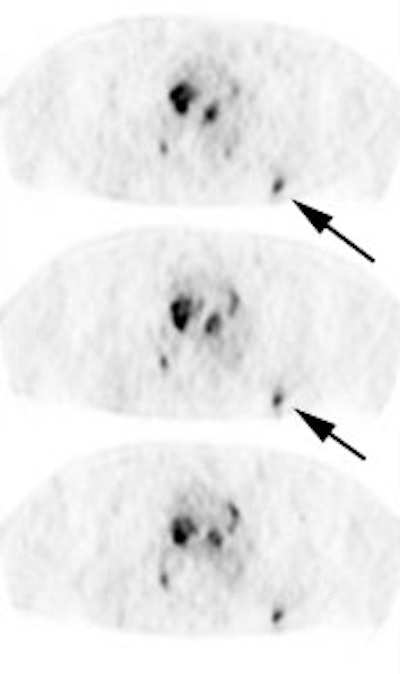

|

Unsuspected bone metastases: The patient shown below had a cavitary left lung non-small cell lung cancer. There was no uptake of tracer within the aortopulmonary window lymph nodes detected on CT to suggest metastases, however, unsuspected bone metastases were found in the left anterior 4th rib (black arrow) and lumbar spine (red arrows- not included in staging lung CT scan). The presence of bone metastases significantly alters patient prognosis and management. PET imaging provides a rapid whole body survey for the detection of unsuspected metastatic disease. |